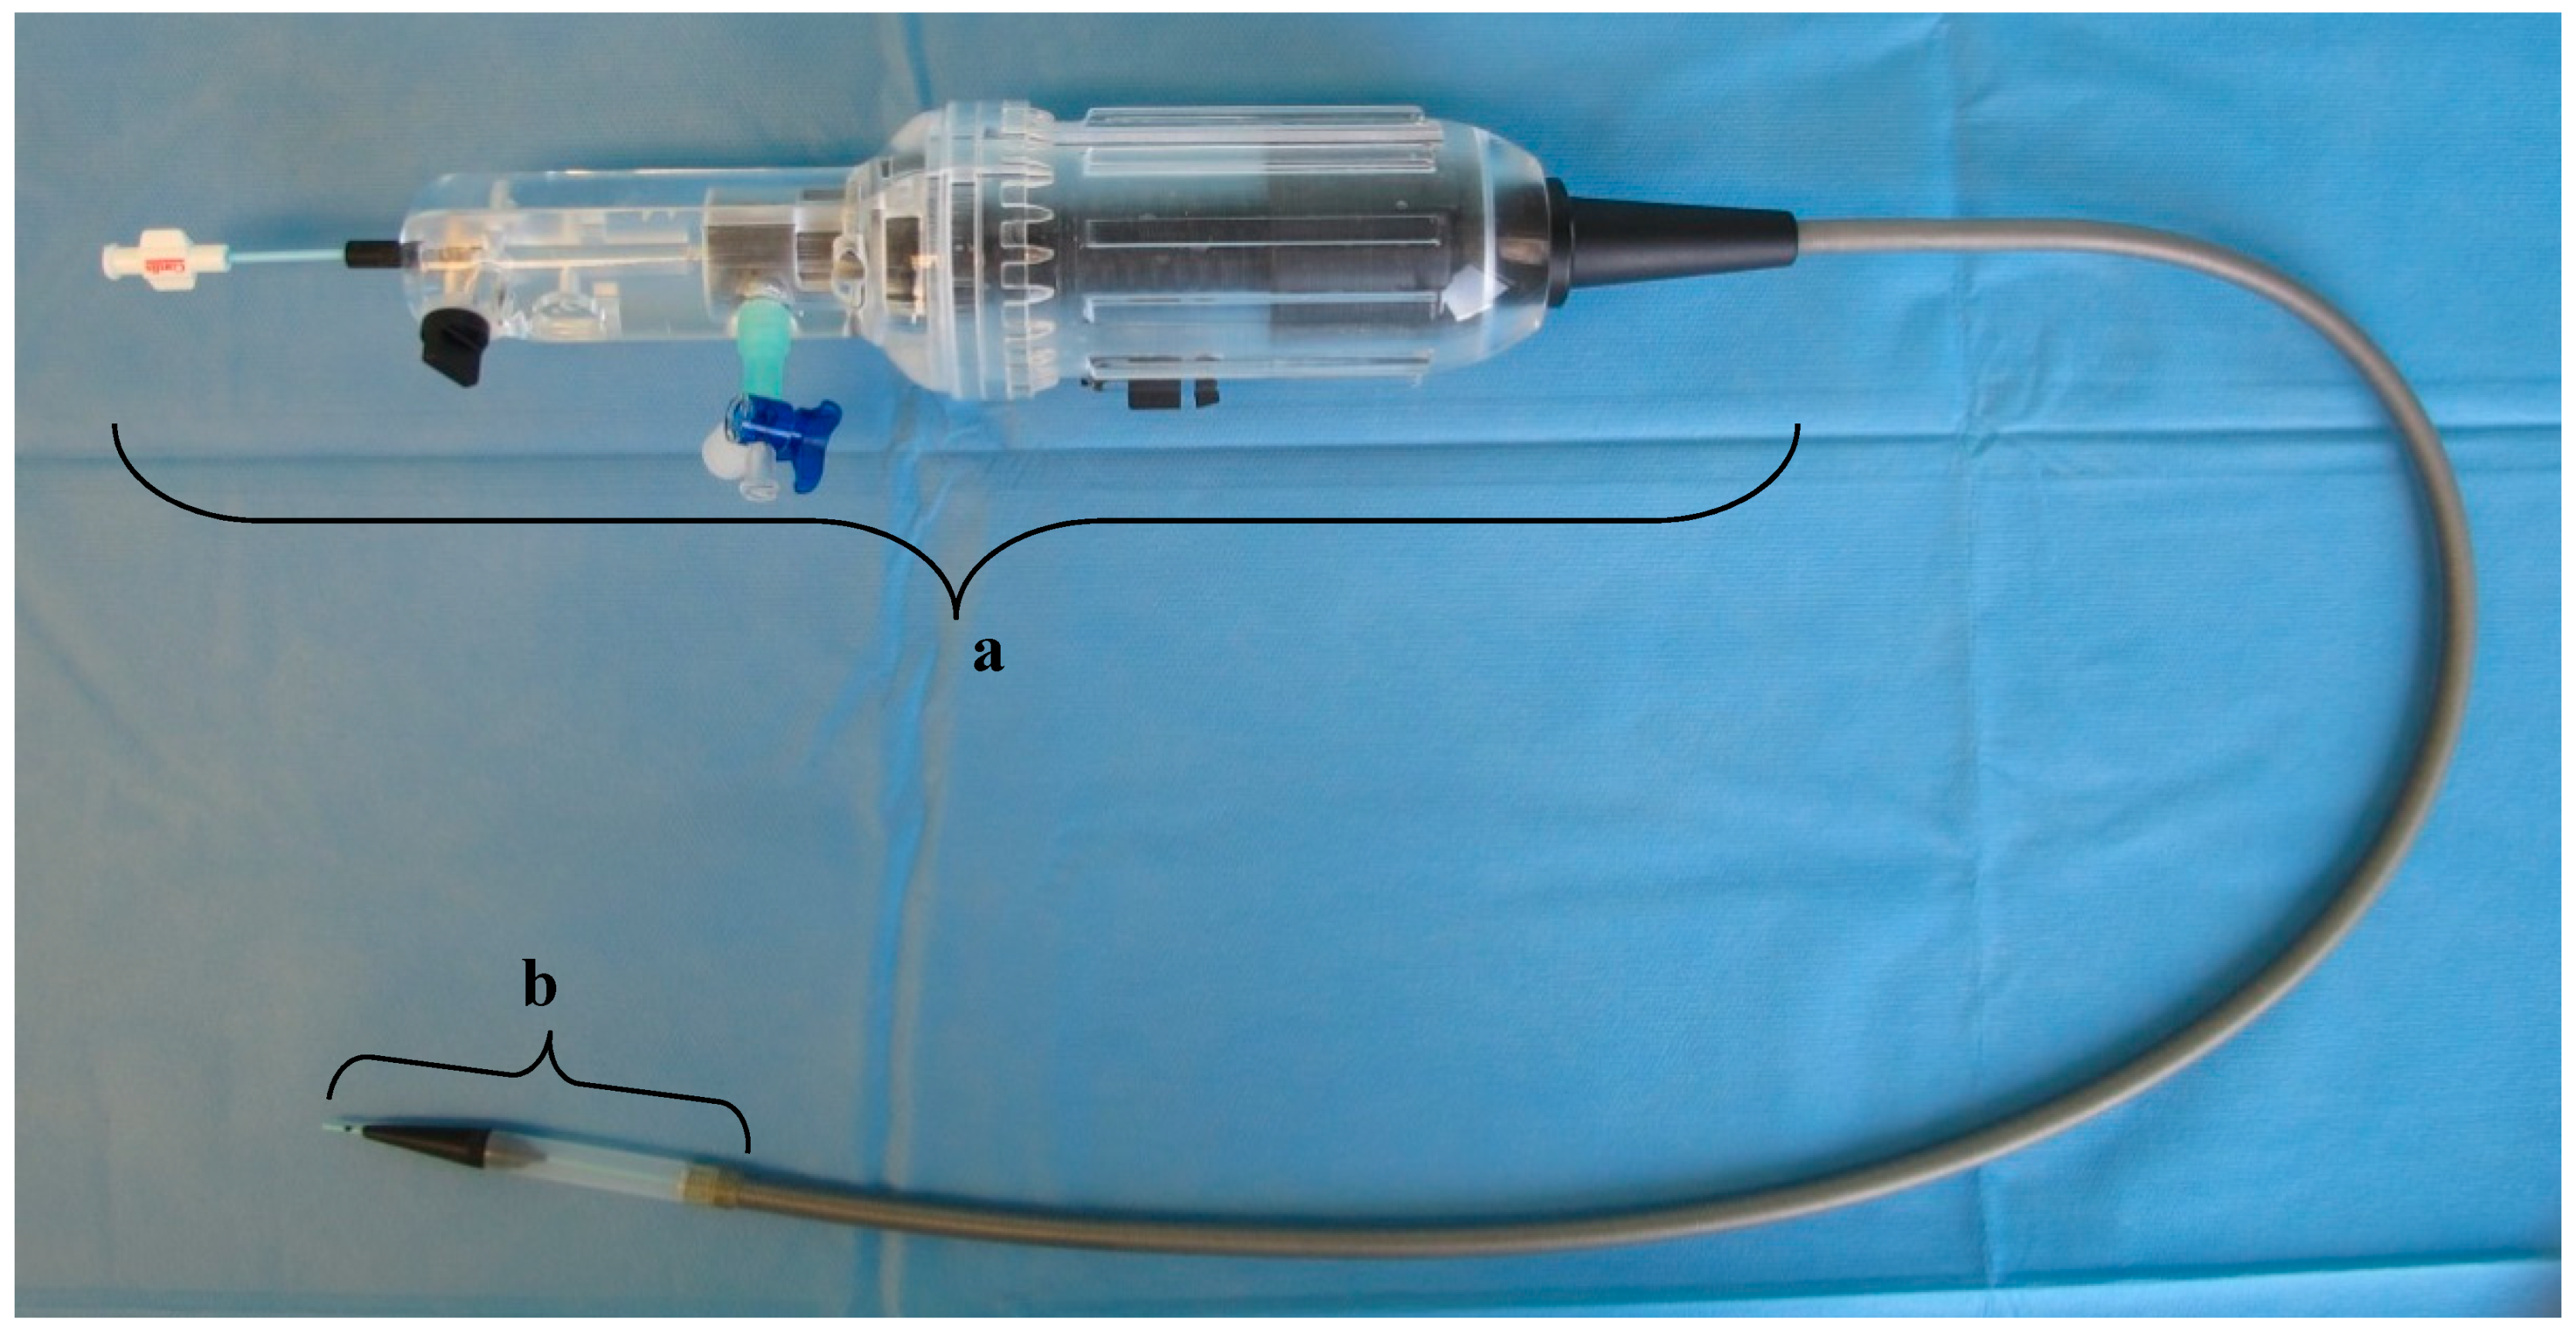

4.2. Delivery System

The dTEHV were implanted minimally invasive into the pulmonary position into sheep, using a custom made delivery system that was introduced through the external jugular vein (Figure 11). This delivery system was developed in order to adequately deploy the stented valve. Specific features have been described in previous publications [23]. In short, the system consisted of an inner sheath made from a steel coil coated with an outer sheath made from a thermoplastic elastomer (Pebax® by Arkema, Colombe, France). At the distal part of these tubes lies the capsule—basically a broadening of the outer sheath—in which the stented valve can be loaded and released. The deployment is performed by pulling back the outer sheath over the inner sheath which functions as a counter bearing for the valve. The process of the deployment can be controlled by the handle which lies on the proximal part of the tube.

Figure 11.

Delivery system designed for the deployment of the dTEHV. The handle is marked with “a”. At the tip of the delivery system lies the capsule in which the dTEHV can be loaded after crimping (marked with “b”). The middle part consists of a steel coil with an outer sheath made from a thermoplastic elastomer.